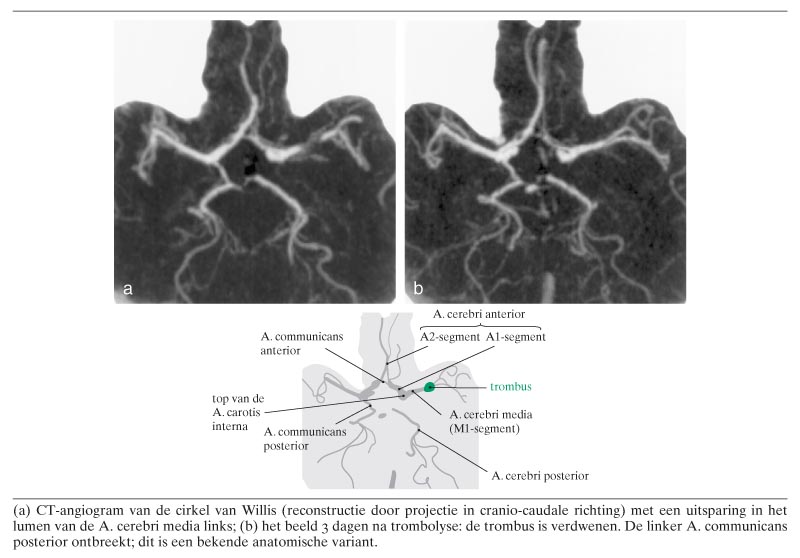

Een 48-jarige vrouw werd door de huisarts verwezen vanwege plotseling ontstaan krachtsverlies van de rechter lichaamshelft. Haar voorgeschiedenis vermeldde cardiomyopathie en een doorgemaakte pericarditis. Bij neurologisch onderzoek had patiënte een voorkeurstand van het hoofd en van de ogen naar links, een gemengde motorische en sensorische afasie en een paralyse van de rechter lichaamshelft. CT-angiografie van de hersenvaten toonde een uitsparing in het lumen van de A. cerebri media links (figuur a), wijzend op een trombus. Patiënte werd 2 h na het ziektebegin behandeld met alteplase 0,9 mg/kg i.v. Na enkele uren verminderde de neurologische uitval en 3…